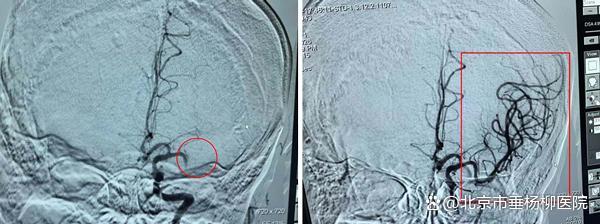

▲术前:红圈处血管阻塞 ▲介入术后:血管畅通

“现在左旗人民都知道,脑血管狭窄需要放支架不用再去赤峰或者北京了。”这句话已成为当地百姓口口相传的安心保障,也彰显了医疗帮扶工作在百姓心中的分量。一面面锦旗、一封封感谢信承载着无数患者康复后的真挚感激。